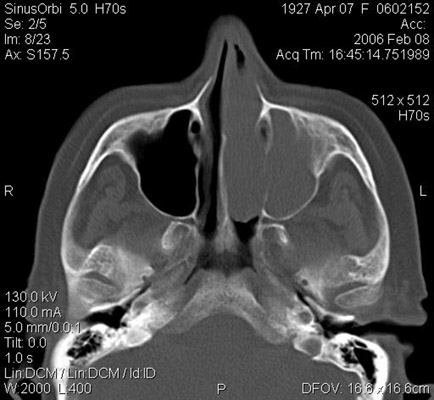

JFC Sinusitis maxilar. Espolón septal.

JFC Sinusitis Maxilar